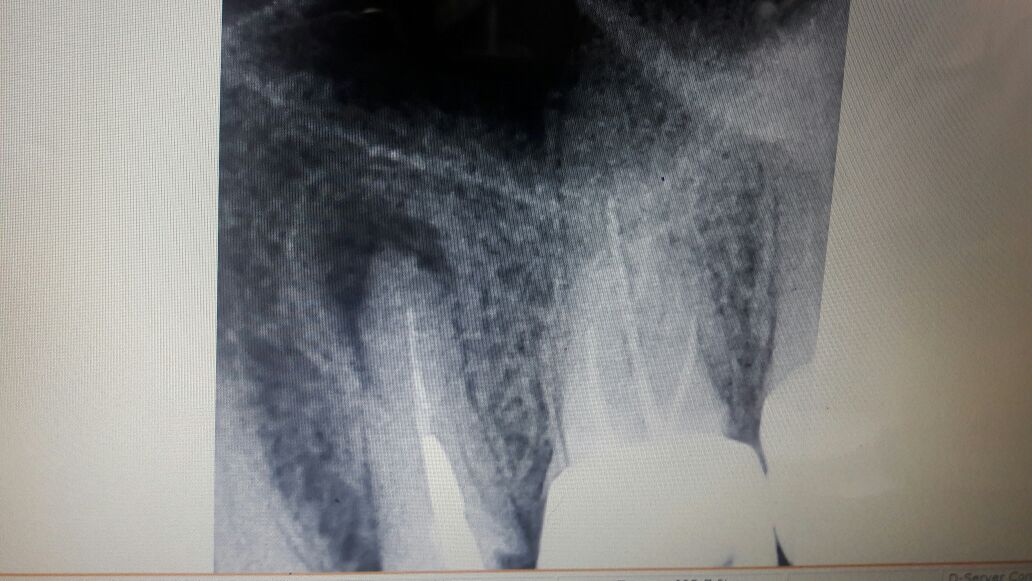

- An X-Ray often reveals need for a RCT.